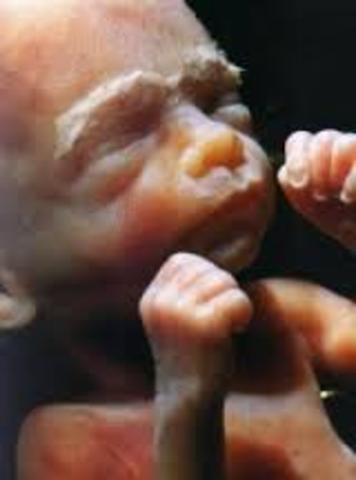

• Month Three

Month Three the baby’s face begins to look more human now and internally, digestive organs are forming. The pancreas, bile ducts and gallbladder have formed by this point. the mother will experience some weight gain but weight gain is normal in pregnancy and should not be discouraged. Morning sickness will still continue for some.